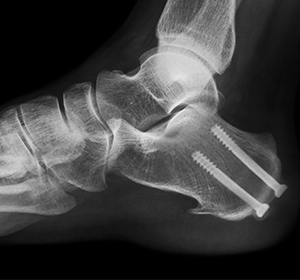

- In this procedure, two or more bones are fused together to provide stability and shape to the foot and ankle joint.

- Tiny wires, pins, or plates may be used to stabilize the bones and keep them in place.